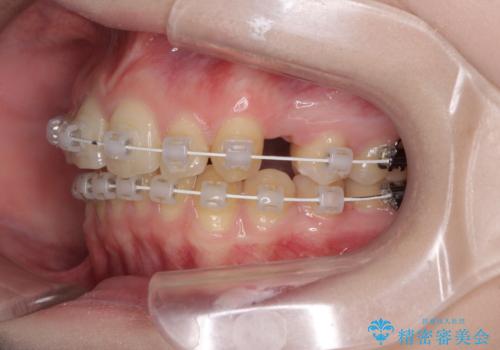

八重歯を短期間で改善 ワイヤー装置による抜歯矯正

- 矯正装置

- 審美装置

- 治療期間

- 1年6ヶ月

- 著しい八重歯を気にして来院された患者様です。

片側の八重歯であり上顎の正中がずれていたため、上顎左右第一小臼歯2本を抜歯して排列することとしました。

下顎の骨格的なズレが大きかったため、上下歯列のバランスが取れるか心配でしたが、上下ともに左右対称に近い歯列で治療を終えることができました。